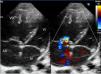

Ingresó en planta de hospitalización con oxigenoterapia, sildenafilo oral y prostaciclinas inhaladas. A los 5días presentó empeoramiento súbito con desaturación y clínica de bajo gasto cardíaco, por lo que se trasladó a la UCI pediátrica. Precisó inicio de ventilación mecánica con FiO2 de 1, tratamiento con óxido nítrico hasta 20ppm y soporte inotrópico con dopamina. En la radiografía se objetivaron líneas B de Kerley e infiltrados moteados perihiliares; en la ecografía torácica se objetivó aumento homogéneo de líneas B, sin condensaciones ni derrame pleural. La ecocardiografía mostró signos de HTP grave (fig. 1) con una estimación de la presión de la arteria pulmonar (PAP) de 70mmHg (VN PAP<20mmHg). Se realizó cateterismo cardíaco que mostró: PAP sistólica/PAP diástolica (PAP media) de 53/24 (38)mmHg (VN PAPs<35mmHg, PAPm<20mmHg)1, resistencias pulmonares de 8,51unidades de Wood/m2 (VN<3UW/m2) y presión de enclavamiento pulmonar (PCP) de 10mmHg (VN<15mmHg)1. Por ello se excluyeron alteraciones del corazón izquierdo como etiología de la HTP.

Ecocardiografía. Eje de 4 cámaras. Cavidades derechas dilatadas con tabique interventricular desviado hacia la izquierda. Insuficiencia tricuspídea moderada con gradiente de 60mmHg que permite estimar una PAP aproximada de 70mmHg. Septo interauricular con foramen oval permeable de 5mm. Válvulas de morfología normal.